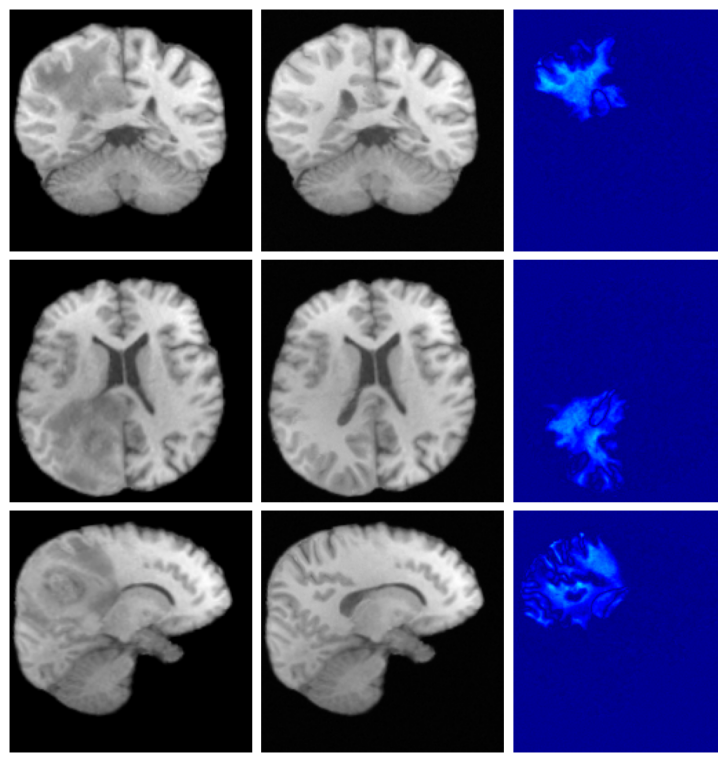

For both the Clinical and Low-field datasets, low-resolution images are skull-stripped and normalized to [-1, 1]. The alignment to MNI space is required by forward model given in Equation 11 and is achieved by recomputing the affine transformation through centroid alignment of anatomical labels from SynthSeg Billot2023 segmentations with the corresponding atlas centroids. Example low-resolution images are shown in Figure 6.

A.8 Additional qualitative restoration results

Additional qualitative results for the Clinical dataset are given in Figures 7, 8 and 9, and for the Low-field dataset in Figures 10 and 11.